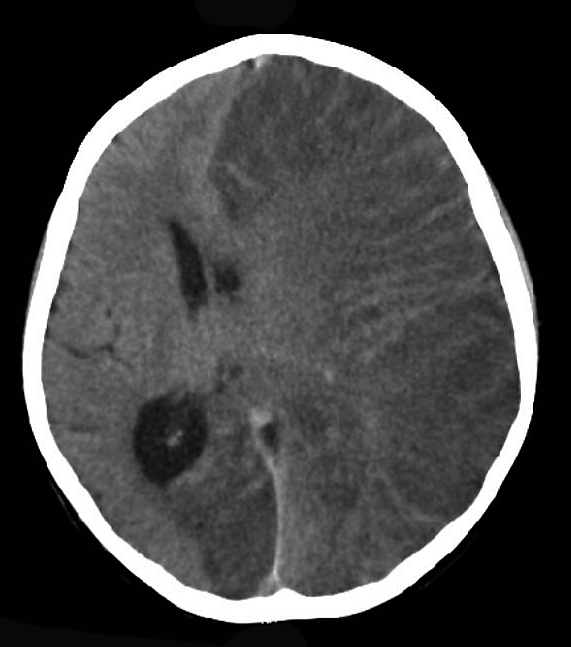

При проведении магнитно-резонансной томографии головного мозга у пациентов с паранеопластическим АЭ характерно выявление гиперинтенсивных очагов на Т2-взвешенных изображениях и в режиме FLAIR. Эти патологические изменения преимущественно локализуются в сером веществе — как в поверхностных отделах коры, так и в глубоких структурах, а также распространяются на прилежащие участки белого вещества. Подобная картина отражает типичное для паранеопластического АЭ поражение центральной нервной системы, при котором аутоиммунный процесс затрагивает как нейрональные структуры серого вещества, так и проводящие пути белого вещества. Особенностью является симметричность и множественность очагов, что помогает дифференцировать эти изменения от других патологических процессов в центральной нервной системе[1].

- патологические изменения при магнитно-резонансной томографии: выявление гиперинтенсивных очагов на Т2-взвешенных изображениях, аномальные сигналы в режиме FLAIR.